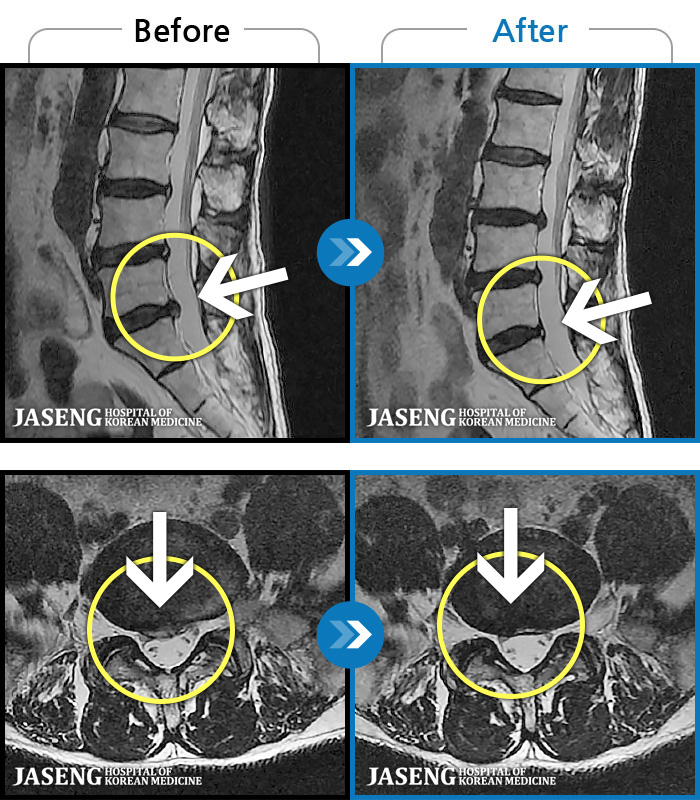

허리디스크

일산 · 김진수 원장

처음 내원 시 허리, 엉덩이가 많이 아프고, 좌측 다리로 근력 및 감각 저하도 있었으며, 야간통을 잠도 못자고 통증 심하여 식사도 무릎꿇고 하는 등 정상적인 활동이 힘든 상태셨습니다.

촬영시기

2022.11.16 ~ 2023.05.24

2023.06.01

조회수 269